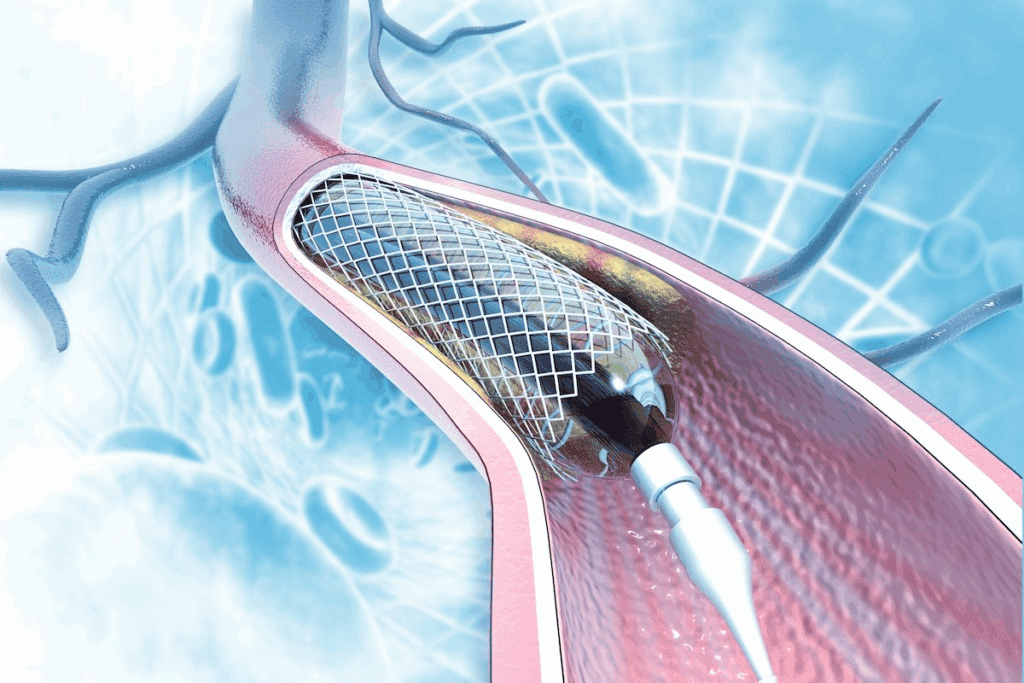

What Happens During the Procedure

A thin, flexible tube called a catheter is used. It goes through an artery in the groin or arm to the blocked artery. A coronary stent, a small mesh tube, is then placed to keep the artery open. This improves blood flow to the heart muscle.

Types of Stents and Their Longevity

There are two main stent types: bare-metal stents and drug-eluting stents. Bare-metal stents are made of metal mesh and keep the artery open. Drug-eluting stents release medication to prevent the artery from narrowing again.

The stent’s lifespan depends on its type and the patient’s health. Drug-eluting stents are often better at preventing artery narrowing than bare-metal stents.

- Bare-metal stents: These are simpler and less expensive but may have a higher risk of the artery re-narrowing.

- Drug-eluting stents: These release medication to prevent re-narrowing and are often recommended for patients at higher risk of artery re-blockage.

Knowing about the different stents and their benefits helps patients understand their treatment. It also highlights the importance of follow-up care for the stent’s longevity and heart health.